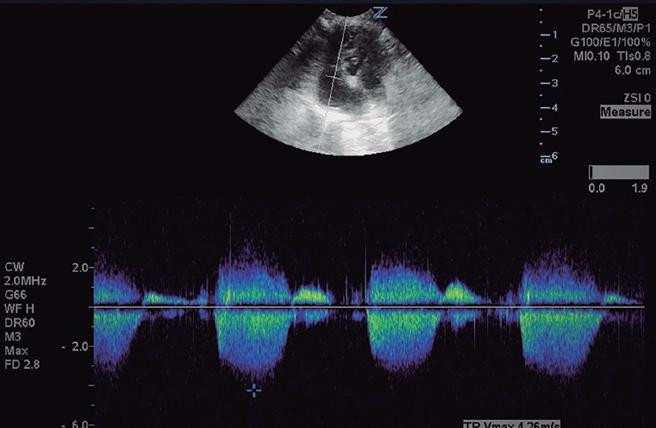

Bloqueantes de canales del calcio Hidralazina, nitratos e IECA